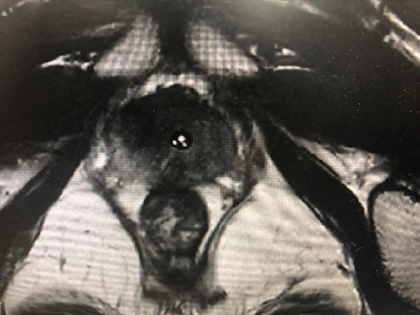

病例六,69岁女性,发现双肾占位10年。10年前于外院发现双肾占位,考虑错构瘤,右肾肿物4cm,定期观察。2周前复查CTU增强提示双肾多发错构瘤,大者位于右肾下极,7.3cm×3.9cm×6.7cm,左侧大者约4.3cm×4.3cm。行机器人辅助腹腔镜双肾部分切除术,术者:张树栋教授、郝一昌教授。术中右肾肿瘤位于肾脏下极,且与肾门关系紧密,仔细分离需小心输尿管损伤。